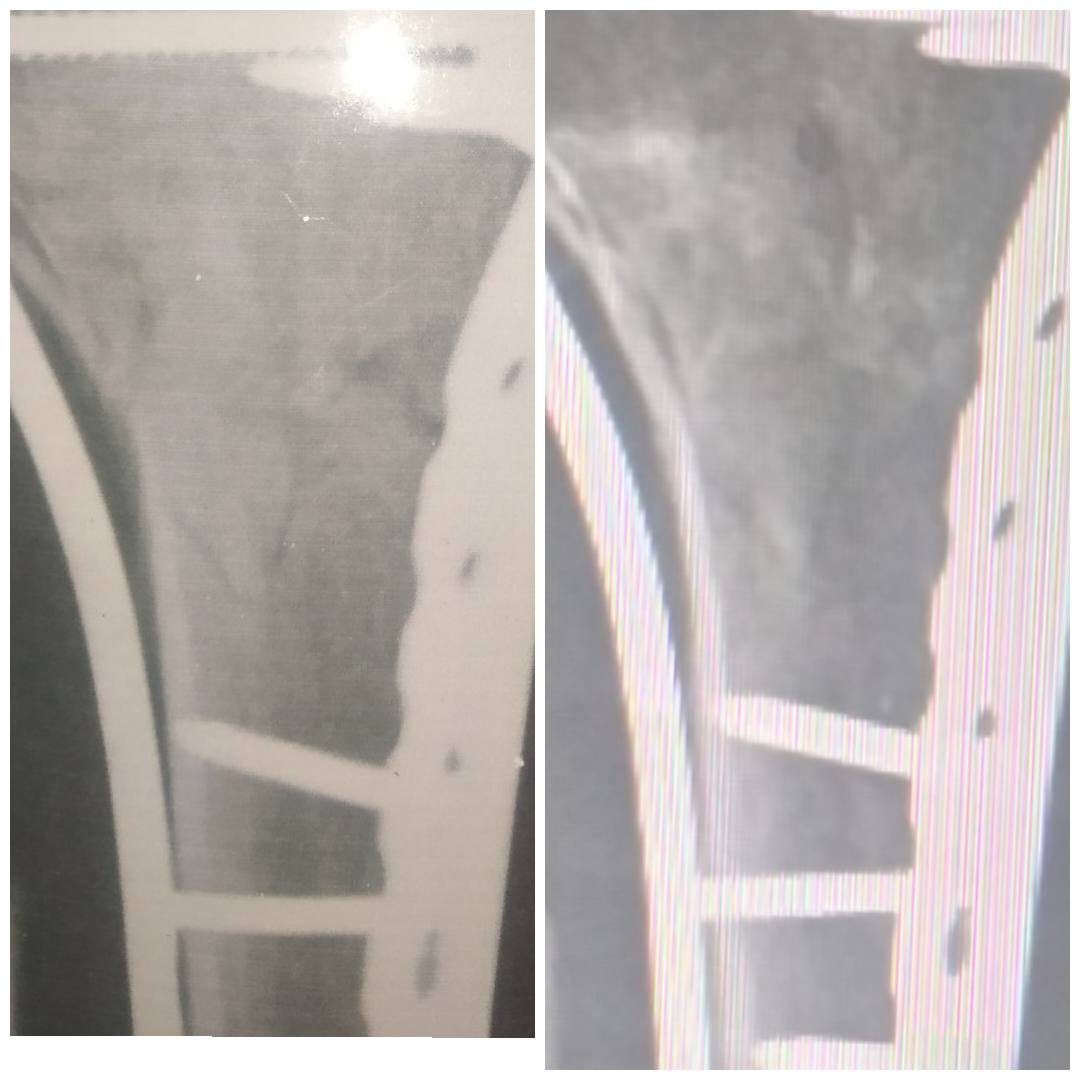

. Following